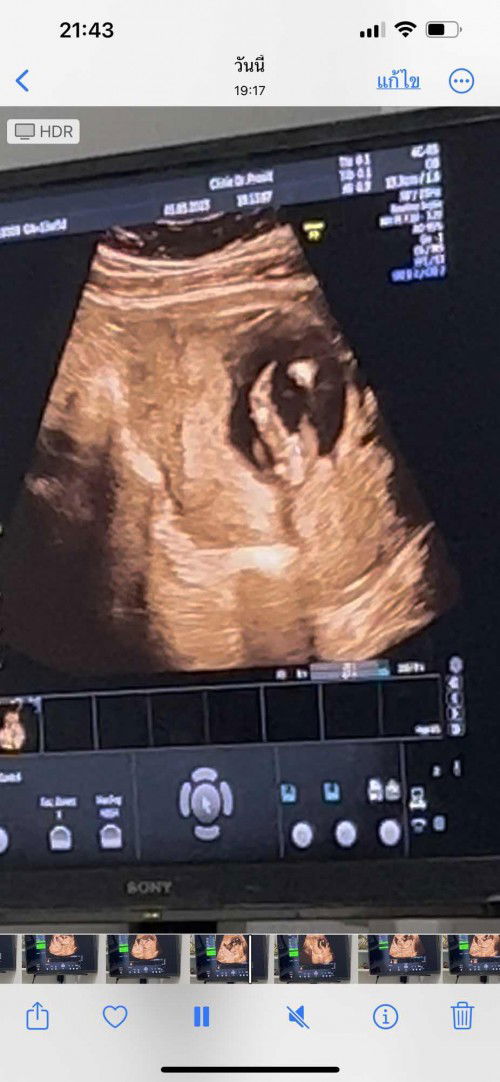

เมื่อวานไปฟังผลเลือดมา คุณหมอบอกว่าเราเสี่ยงสูง 1:169 ต้องส่งตัวเจาะน้ำคร่ำ พอได้ฟังรู้สึกใจสลาย เสียใจมากๆเลยค่ะ ร้องไห้จนไม่มีน้ำตาแล้ว มีแม่ๆคนไหนมีประสบการณ์แบบนี้มั้ยคะ โอกาศที่ผลเจาะน่ำคร่ำออกมาปกติ มีมั้ยคะ 😢😢😢 (เราอายุ24 แฟน31ค่ะ) #16w3d #ผลเลือดเสี่ยงสูง #ดาวน์ซินโดรม #ขอประสงการ์ณแม่ๆหน่อยคะ #ขอบคุณสำหรับคำตอบค่ะ